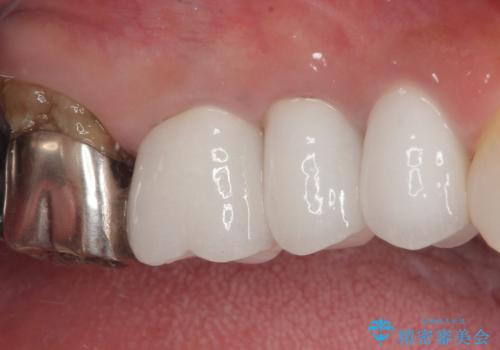

奥の銀歯の幅が大きかったこともあり、細長いクラウンの見た目は大きく改善することができました。

今後は他の銀歯の治療を進めていく計画です。